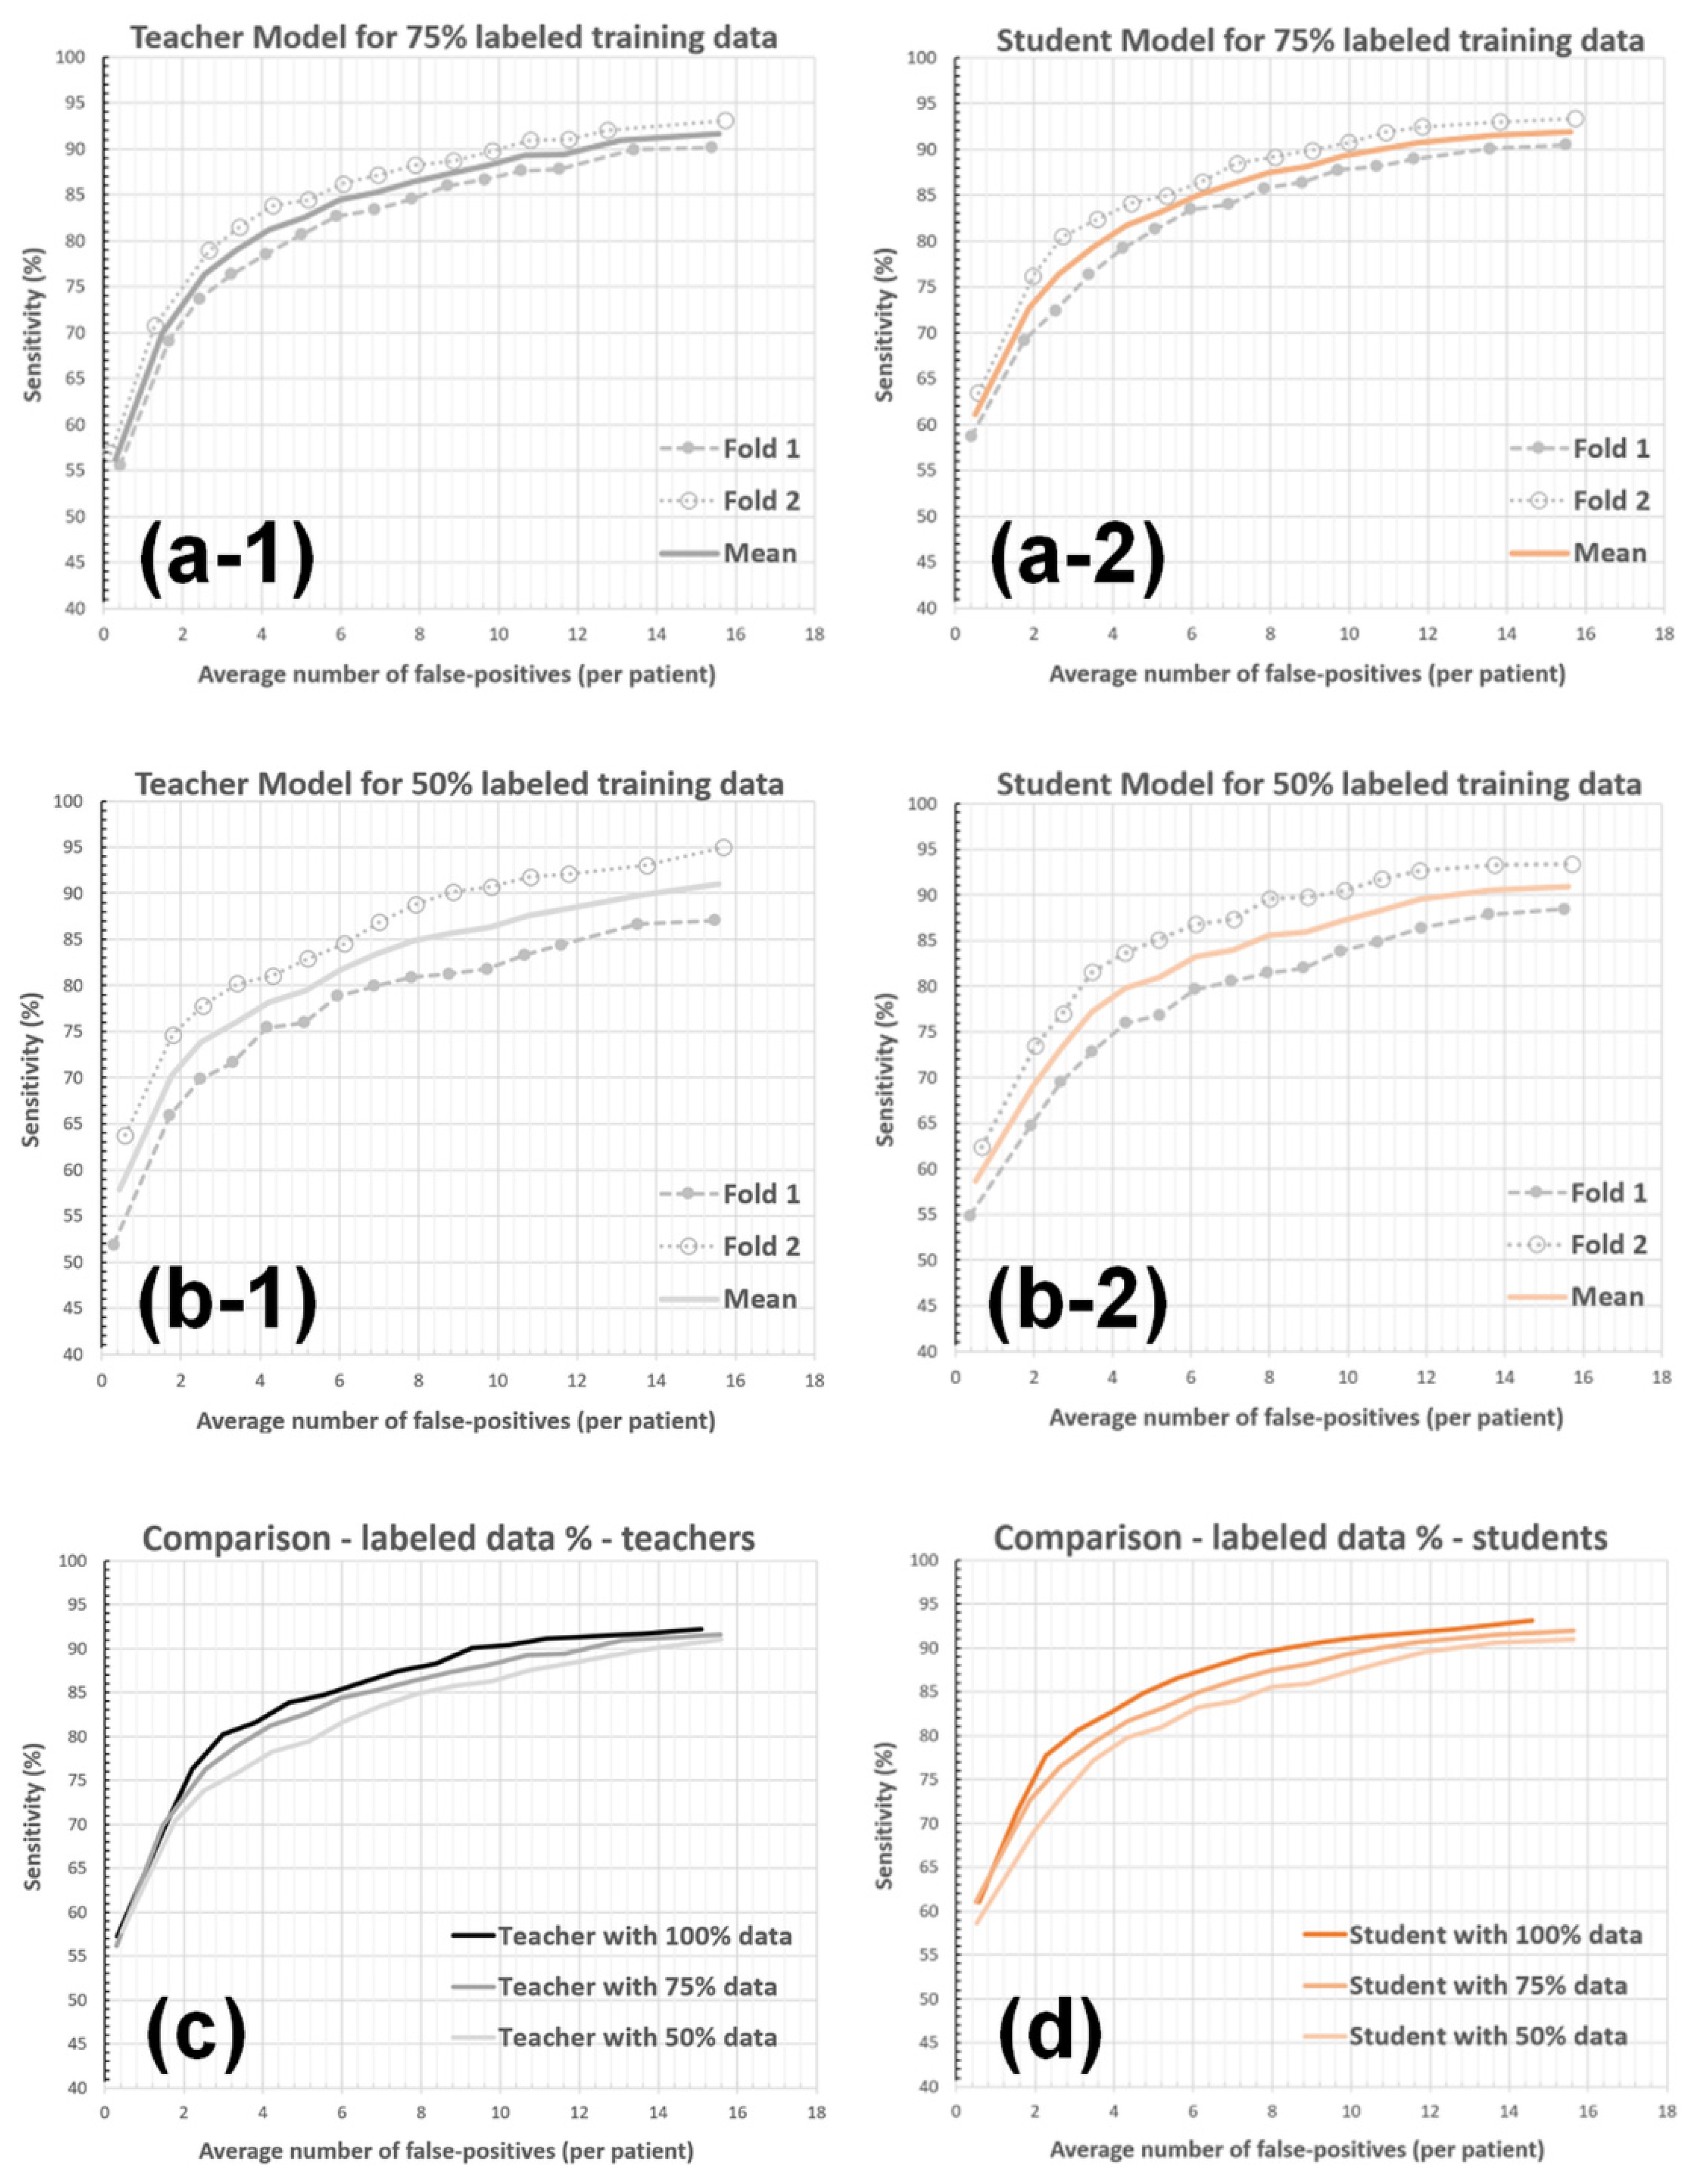

3.2. Experiments with System Parameters

3.2.4. Labeled-Data Utilization